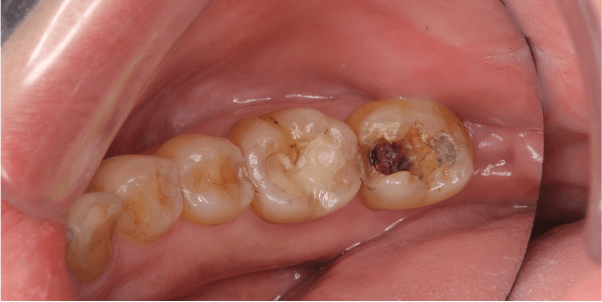

40歳女性のビフォーアフター

| 診断 | インレー脱離(被せものが取れた)、カリエス(虫歯) |

|---|---|

| 治療方針 | カリエスを除去し、形を整えた後にセラミックインレーを装着 |

| 治療費 ※ | 55000円(税込) |

| 治療期間 | 1カ月 |

| リスク | 割れるリスクあり |

※ 治療費は、治療当時の費用で、現在の費用と異なる可能性があります。現在の費用は治療費のページでご確認くださいませ。